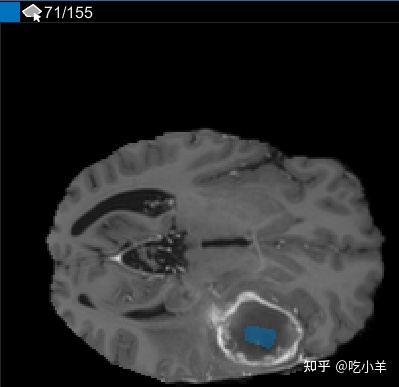

使用插值后,检查单个切片以查看插值是否创建了令人满意的 ROI。请注意,切片 71 上的 ROI 并未填充您要分割的整个对象。您可以使用手动调节ROI画笔工具。或者,您可以使用“自动化”选项卡上的工具之一。例如,您可以使用Active Contours在未填充肿瘤全尺寸的切片上增加 ROI。

在切片窗格中,导航到对象第一次出现的切片,并开始使用绘图工具在每个切片上标记对象。在下图中,本示例使用画笔工具标记肿瘤。和以前一样,您可以在对象出现的每个切片上绘制对象,或者使用插值工具自动在多个切片上绘制。插值后,您可以使用绘图工具,例如橡皮擦,修改每个切片上的自动分割。